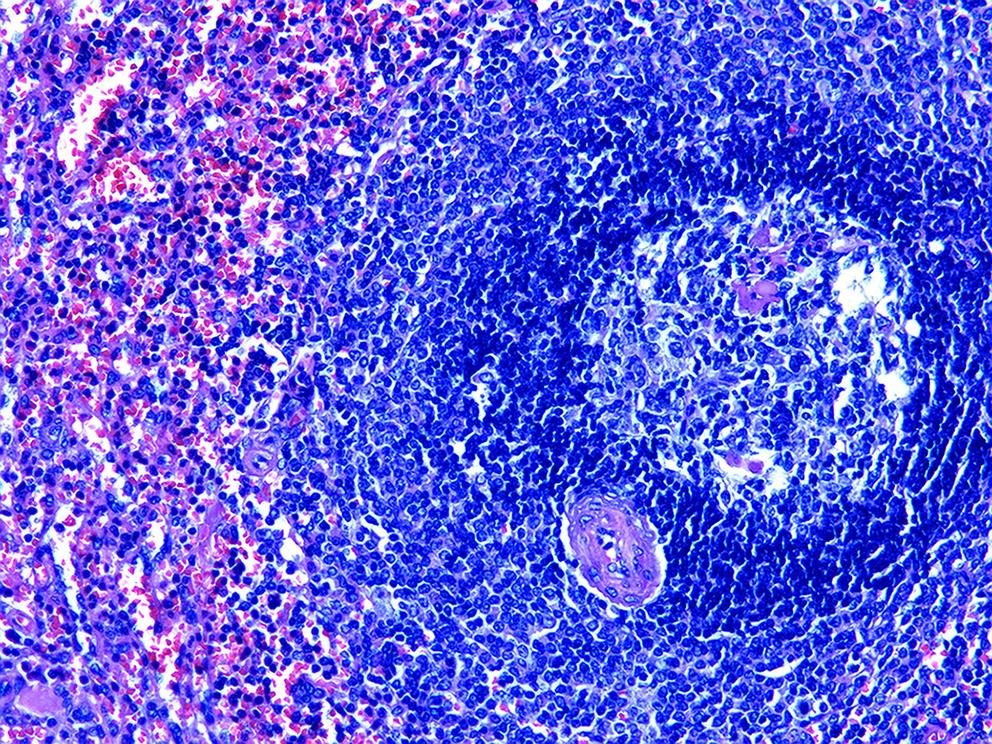

胰腺内副脾误诊2例报告

摘要(1364) HTML (331) PDF (1188KB)(158)

副脾是指正常脾脏以外存在的,与主脾结构相似,有一定功能的脾脏组织,其中完全被胰腺包裹的胰腺内副脾(IPAS)发生率仅为2%,因其临床症状不典型,影像学特征与胰腺神经内分泌肿瘤、胰腺实性假乳头状瘤以及其他胰腺占位性病变较为相似,临床上容易误诊。本文报道了2例分别被误诊为胰腺神经内分泌肿瘤和胰腺实性假乳头状瘤的IPAS患者,并分析误诊原因,总结诊疗经验,以期提升临床对IPAS明确鉴别诊断的认识。